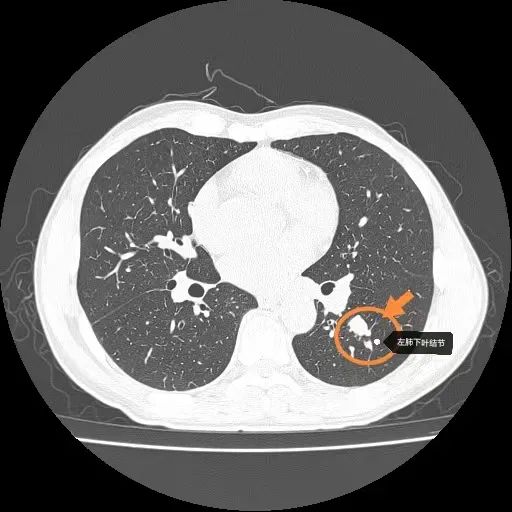

胸部CT

左肺下叶结节